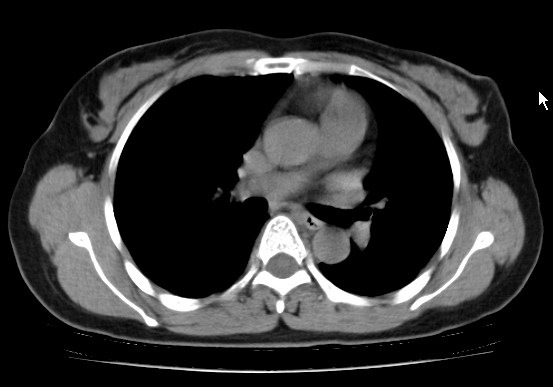

标题: CT25227:背部疼痛伴双侧胸壁痛2月,食欲差。 [打印本页]

标题: CT25227:背部疼痛伴双侧胸壁痛2月,食欲差。

肺结核并胸椎结核?请各位高手指教。

考虑胸椎结核并椎旁软组织肿胀。

左肺结核灶,胸椎结核并冷脓肿。

左肺结核灶,胸椎结核并冷脓肿

椎旁软组织肿胀。

考虑胸椎结核并椎旁软组织肿胀。 支持